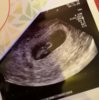

Varhaisultra

Asun Kanadassa ja taalla melkein kaikki paasee ultraan hetimiten. Itsekin menossa 3.1, sillon viikkoja 8+. Ja ilmeisesti tassa raskaudessa paasen ultraan aika tiuhaan, silla viime raskaus paattyi myohaiseen keskenmenoon, tai voi ehka kutsua jo kohtukuolemaksi kun viikkojakin oli jo 20.

Minulle enemmänkin varhaisultra on nämä alle 10 viikoilla tehdyt ultrat, lisääntymislääketieteen yksiköstä jossa olimme asiakkaina kun soittelin plussasta, varattiin aika nimenomaan alkuraskauden varhaisultraan jossa varmistettiin että siellä on tyyppi oikeassa paikassa kasvamassa. Niskapoimu-ultra varataan sitten neuvolassa joskus.

Huh. Jännää miten monilla siel onki jo näkyny kaikenlaista ja itellä ei näkyny tosiaan viel mitään ku 17.12 kävin. Noh,saatiin sentää uus aika 2.1. :) mut silti nyt ehkä alkaa pienoinen paniikki nostaa päätäö. Viikkoja PITÄIS olla ehkä sen 4+2 nyt,joten se ois joku 6+3 (???) silloon 2.1, ni ehkä sitten jotaki konkreettista jopa löytyisikin.

Jos etenis kuukautisista laskettuna normaalisti niin pitäis olla 6+6. Ainakin syke pitäis näkyä ja hurja kasvu viime viikosta.